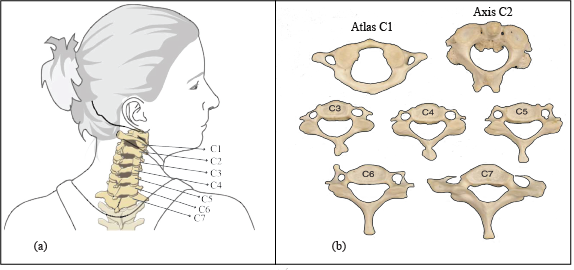

The neck is a part of the spinal column, a long, flexible structure that runs through most of the body. The cervical spine, or neck region, is made up of seven bones called vertebrae, which are separated by intervertebral discs as presented in Figure 1. The third through the sixth cervical vertebrae show nearly identical features and are therefore considered typical of this region. The upper two cervical vertebrae, the atlas (C1), the axis (C2), and the seventh cervical vertebra (C7) are atypical. Typical Cervical Vertebrae (C3 to C6) have small rectangular bodies made of a relatively dense and strong cortical shell. the primary function of C1 is to support the head. (C2) has a large, tall body that serves as a base for the upwardly projecting dens. Vertebra Prominens (C7) is the largest of all cervical vertebrae, having many characteristics of thoracic vertebrae [1].